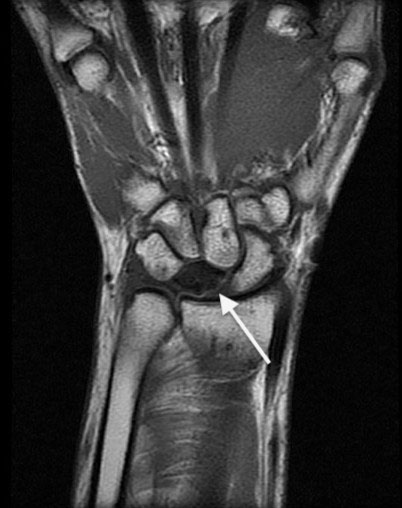

El diagnóstico de la enfermedad de Kienböck a menudo se puede hacer revisando su historial clínico, realizando una buena exploración física y realizando unas radiografías. En las primeras etapas de esta enfermedad, las radiografías pueden ser normales y se necesitan otras pruebas para confirmar el diagnóstico. Lo más probable es que la prueba más fiable para evaluar el flujo sanguíneo del semilunar sea la resonancia magnética (RM) (Figura 2). También se pueden usar la tomografía computarizada (TAC) y la gammagrafía ósea.

Figura 2 - Imagen de RM en la que se observa el hueso semilunar sin flujo sanguíneo.